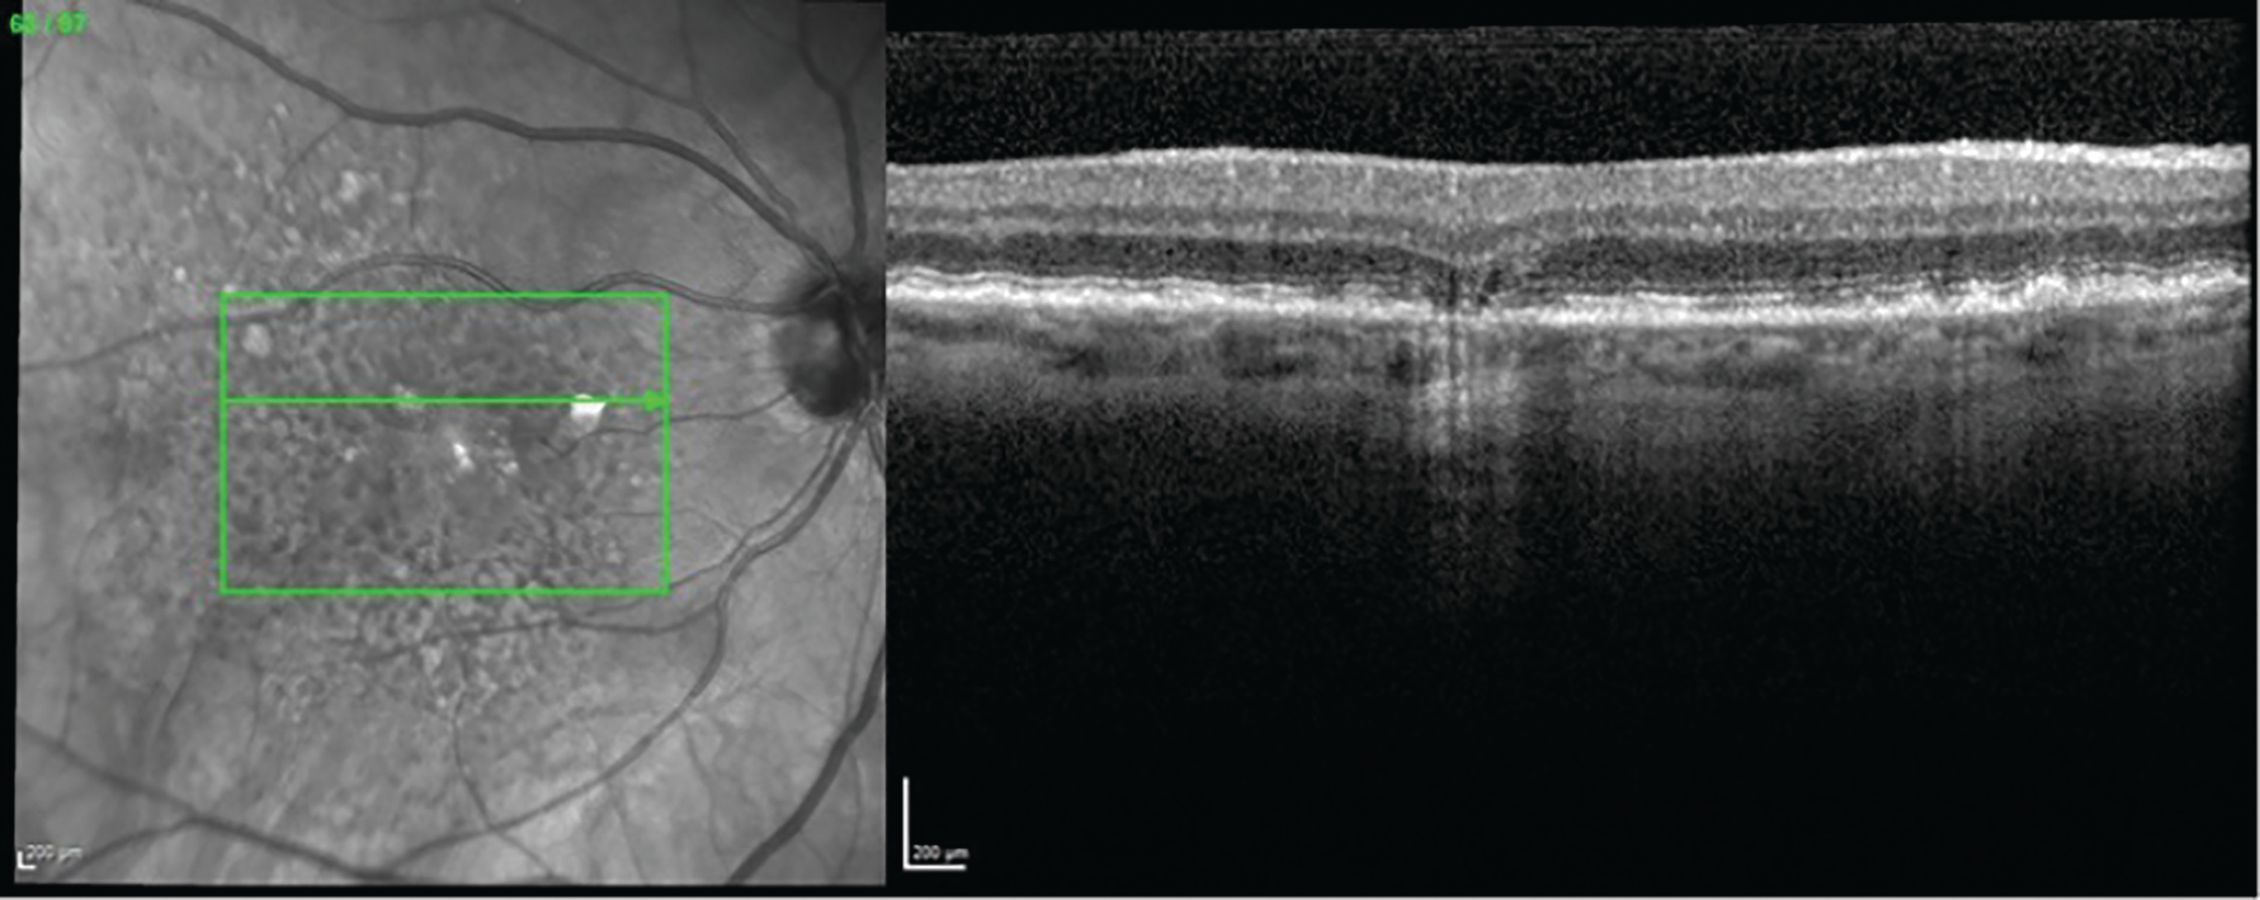

Tunde Peto, MD, PhD, discussed two of her presentations at EURETINA 2022: "UK Biobank retinal imaging grading: methodology, baseline characteristics and findings for common ocular diseases" and "Retinal phenotyping of different variants of Alzheimer’s disease using ultra-widefield imaging."